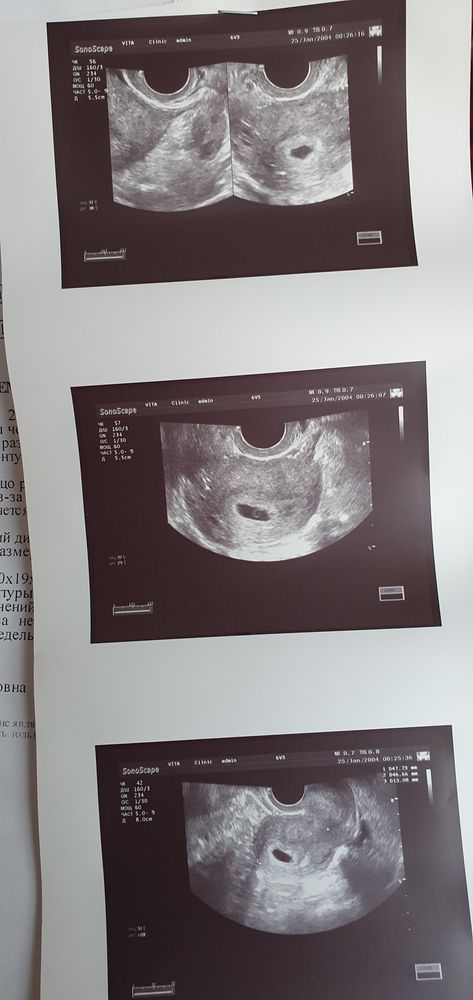

8й ДПП ХГЧ 98, 10й ДПП - 269, 13й - 1107. Подсаживали 2х пятидневок. Вроде как, тьфу-тьфу-тьфу, пока что все хорошо, один прикрепился, но мне вот интересно, могли ли второго проглядеть 🤔

У меня второе ПЯ появилось позже, через дня 3 после того как увидели первого, но к сожалению оказалось пустым, эмбрион был только в одном ПЯ

Анна, ого, второе то большое какое, либо ракурс такой.. По сути, конечно, главное чтобы и один был, главное, здоровый и всё с ним было бы хорошо 🙂

Анна Шанберова, да, ракурс такой, по факту оно было меньше первого, но не намного, по месячным одно шло в срок, а втрое отставало на 3-4 дня, и там не было ЖМ